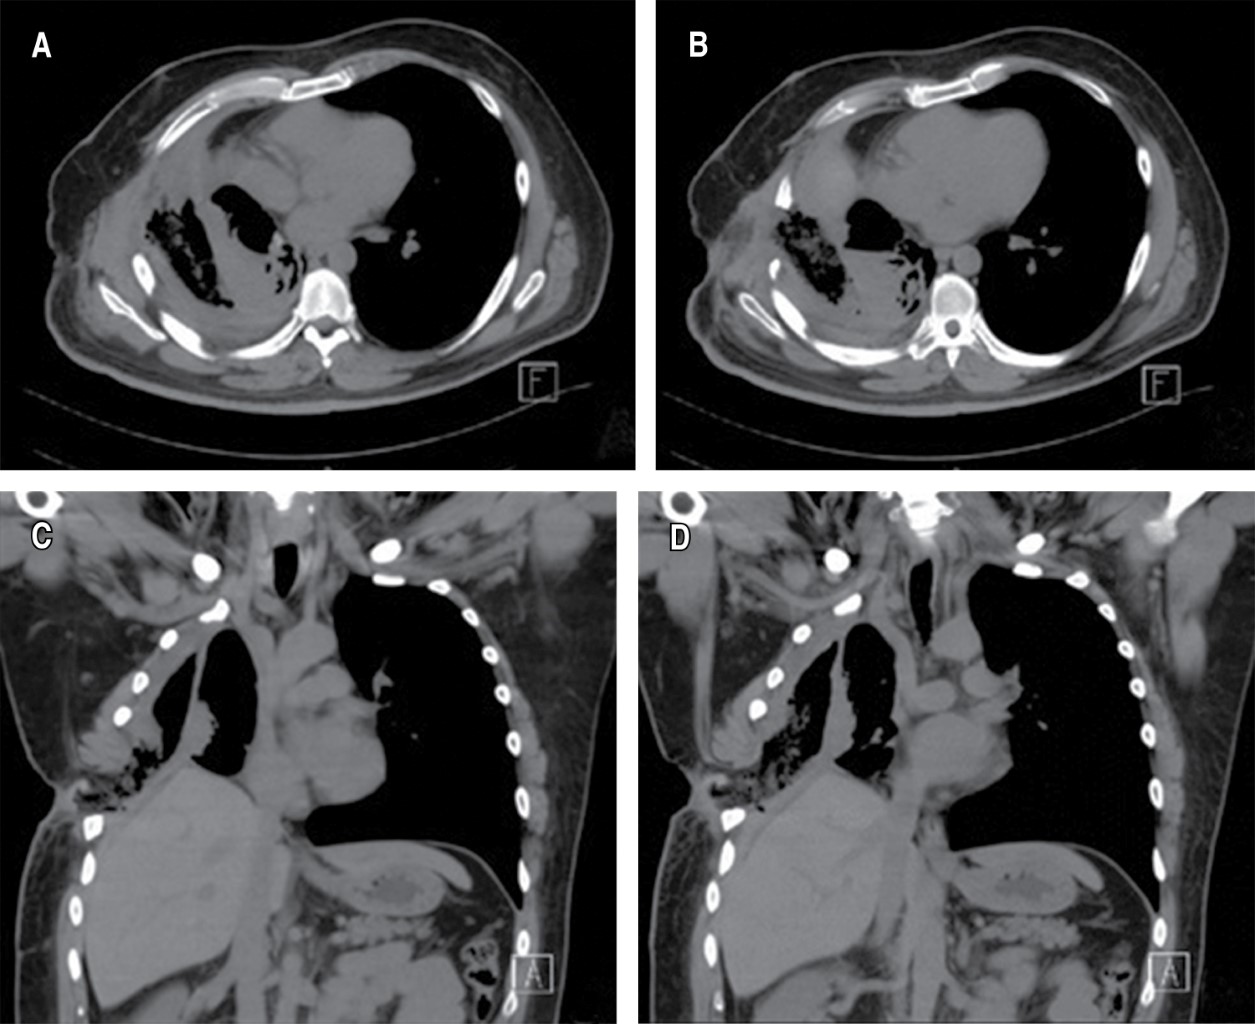

Hombre de 49 años, originario y residente del Estado de México, ocupación: personal de mudanza de equipos de lavandería en hospitales, cárceles y asilos, COMBE negativo, consumo de alcohol negado, tabaco a razón de un cigarrillo por día durante 21 años (IT 1.05). Antecedente de diabetes tipo 2 diagnosticado en 2005, tratado con insulina glargina 20 UI y metformina/glibenclamida. Tuberculosis pulmonar y pleural diagnosticada en mayo de 2017, tratado con IRPE durante un año, actualmente en remisión. Fístula broncopleural derecha de alto flujo y neumotórax espontáneo diagnosticado en junio de 2017, tratado con toracotomía y fistulectomía, ameritando una segunda intervención por persistencia; actualmente en remisión. Derrame pleural tratado con toracotomía y colocación de sonda en junio de 2017 por persistencia de derrame pleural; se realizó ventana torácica con técnica de Eloesser en octubre de 2017, en la actualidad en remisión y en espera de cierre quirúrgico. Fue referido al servicio de cirugía plástica el 17 de octubre de 2018 para valorar cierre de ventana pleural. A la exploración física se observó área cruenta de aproximadamente 6 × 7 cm en la región lateral de tórax derecho, cubierto con sistema de presión negativa, sin datos de fuga y con gasto serohemático. Tórax normolíneo, amplexión y amplexación asimétricas a expensas de hemitórax derecho, disminución de ruidos respiratorios y vibraciones vocales basales derechos, hemitórax izquierdo sin compromiso; el resto de la exploración sin anormalidades. Contaba con espirometría del 03 de octubre de 2018, que reportó evidencia de patrón restrictivo moderadamente severo, con una capacidad vital forzada (FVC) de 58.4 (Tabla 1) y tomografía de tórax realizada el 06 de octubre de 2018, que reportó ventana pulmonar con engrosamiento pleural y presencia de líquido heterogéneo, acompañado de neumotórax derecho (Figura 1 A-D). En el quirófano se realizó el 22 de octubre de 2018 cultivo, que no reportó crecimiento de patógenos y se decidió la colocación de sistema de presión negativa con esponja hidrofóbica de poliuretano. Cuatro días después se decidió realizar reconstrucción tardía mediante colgajo dorsal ancho pediculado para cierre de ventana pleural (Figura 2 A-F). El paciente evolucionó favorablemente, por lo cual fue dado de alta el 31 de octubre de 2018. Se dio seguimiento cuatro meses después de la cirugía, solicitando una espirometría, que reportó patrón restrictivo moderado (Tabla 2), con una FVC de 64.6, mostrando una mejoría de 11% comparado con el estudio previo y una tomografía de tórax donde se observaba el cierre de la ventana pleural (Figura 3 A y B).

Figura 1